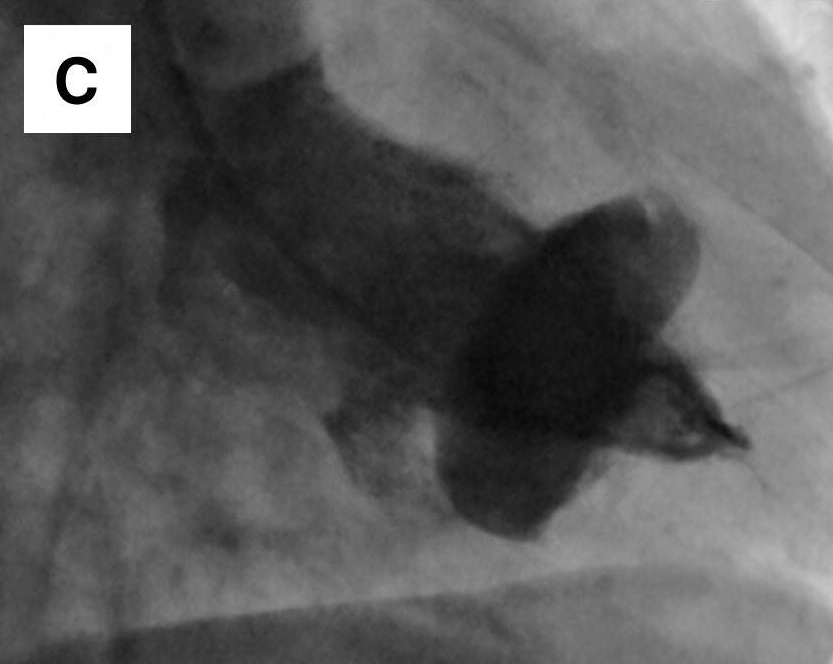

患者女性,69岁,因体检心电图发现T波改变,到心脏科就诊。患者既往无心脏相关病史及心血管危险因素。超声心动图检查发现室间隔肌部瘤样膨出,未发现左向右分流。冠状动脉造影证实冠状动脉正常。左心室造影可见室间隔肌部瘤形成。进一步行心脏CTA及MRI检查,结果显示巨大室间隔肌部瘤,直径与胸主动脉直径相当,未见血栓形成。鉴于患者无症状且无血流动力学影响,采取保守治疗策略,包括生活方式干预、定期心脏监测及规律随访。虽考虑预防性抗凝治疗可能会获益,但由于无血栓形成、血流动力学稳定且缺乏其他危险因素,最终未予实施。不抗凝虽可能增加血栓形成风险,但瘤体内的血流状态可能减少了血栓形成机会,避免了抗栓治疗相关的出血风险。嘱患者每6个月复查超声心动图,必要时行MRI检查。随访期间患者持续无症状且无新发异常,故继续维持原监测方案。

图为心电图、冠状动脉造影、经胸超声心动图、CTA及MRI检查结果。心电图显示v2-4导联T波改变(图A)。左心室造影可见室间隔肌部瘤(图C)。超声心动图显示室间隔瘤样结构(图D)。CTA与MRI均显示巨大室间隔肌部瘤(图E、F)。